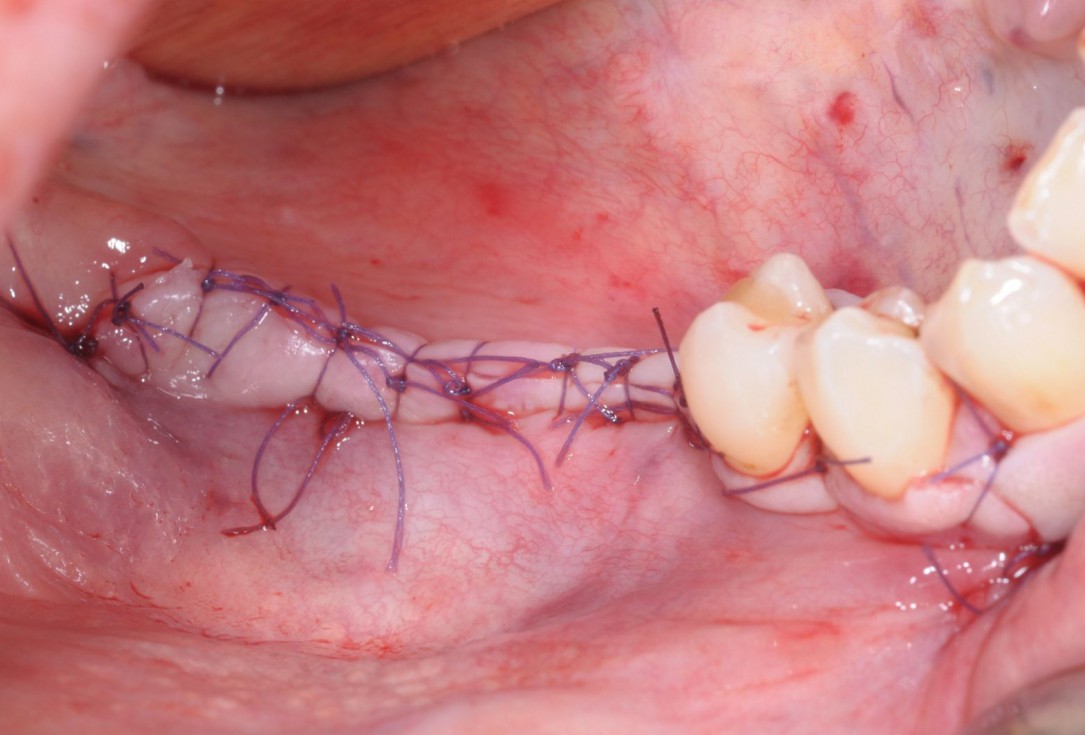

10/28 - Saliva-tight and compression-free wound closure with single-button and mattress suturesThree-dimensional augmentation with maxgraft® cortico - Dr. R. Würdinger